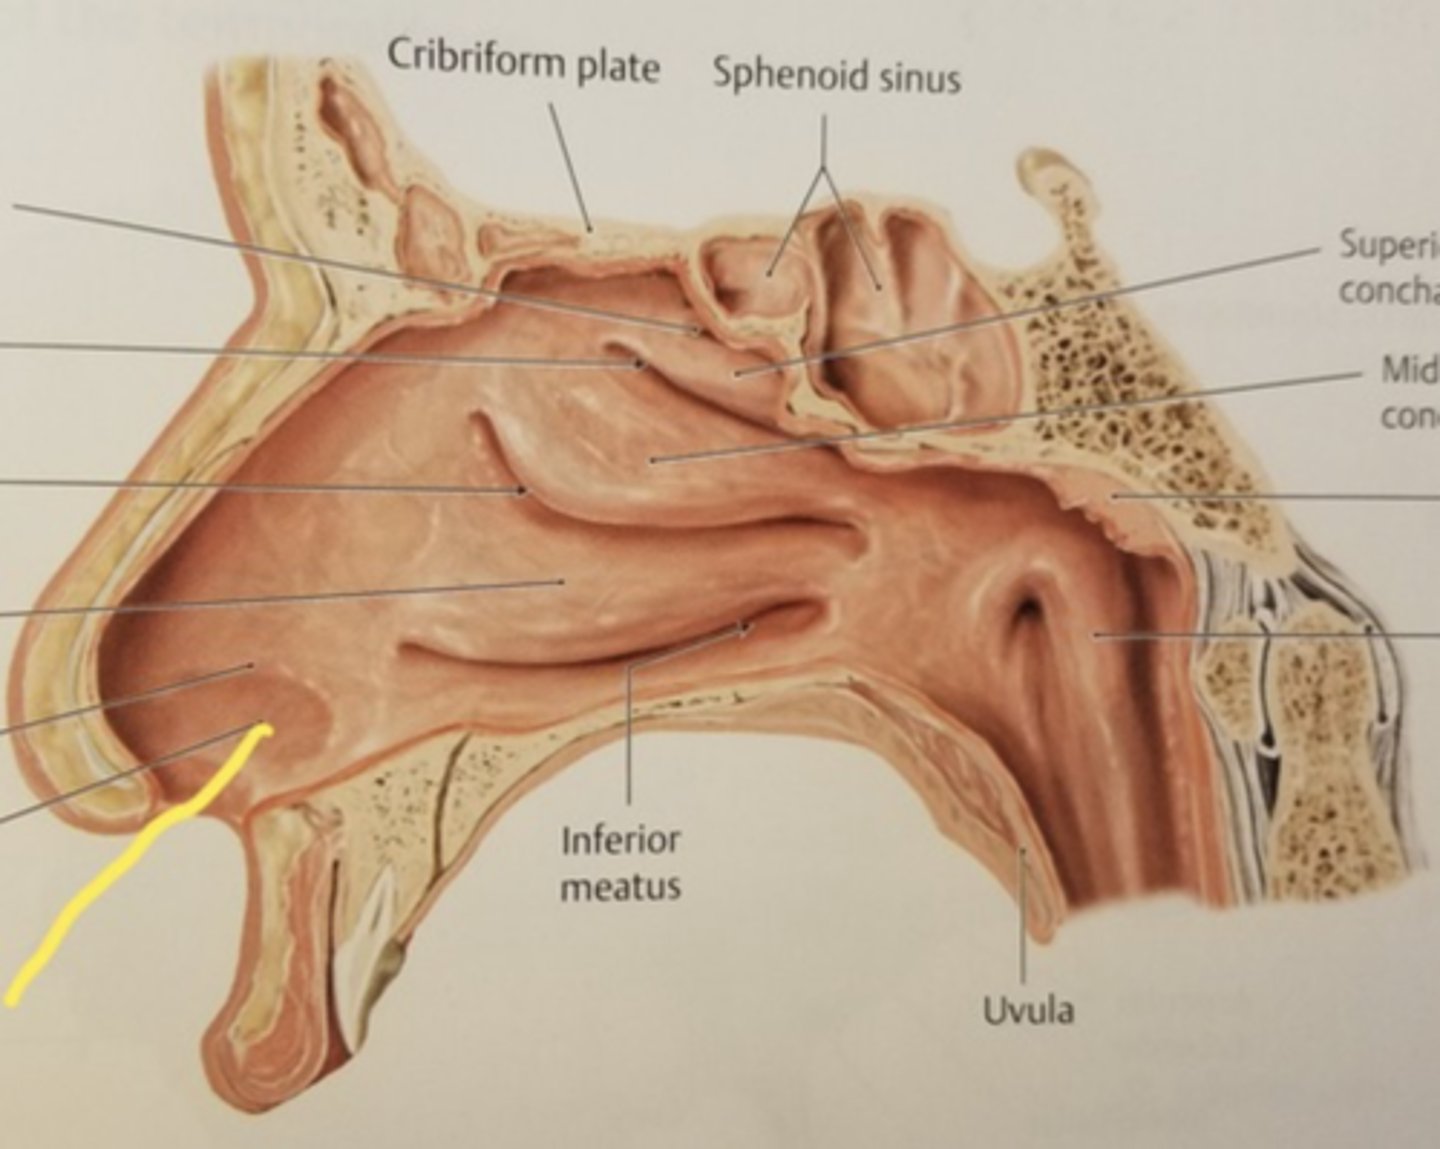

nose

external nares

vestibule

superior nasal conchae

middle nasal conchae

inferior nasal conchae

nasopharynx

oropharynx

laryngopharynx